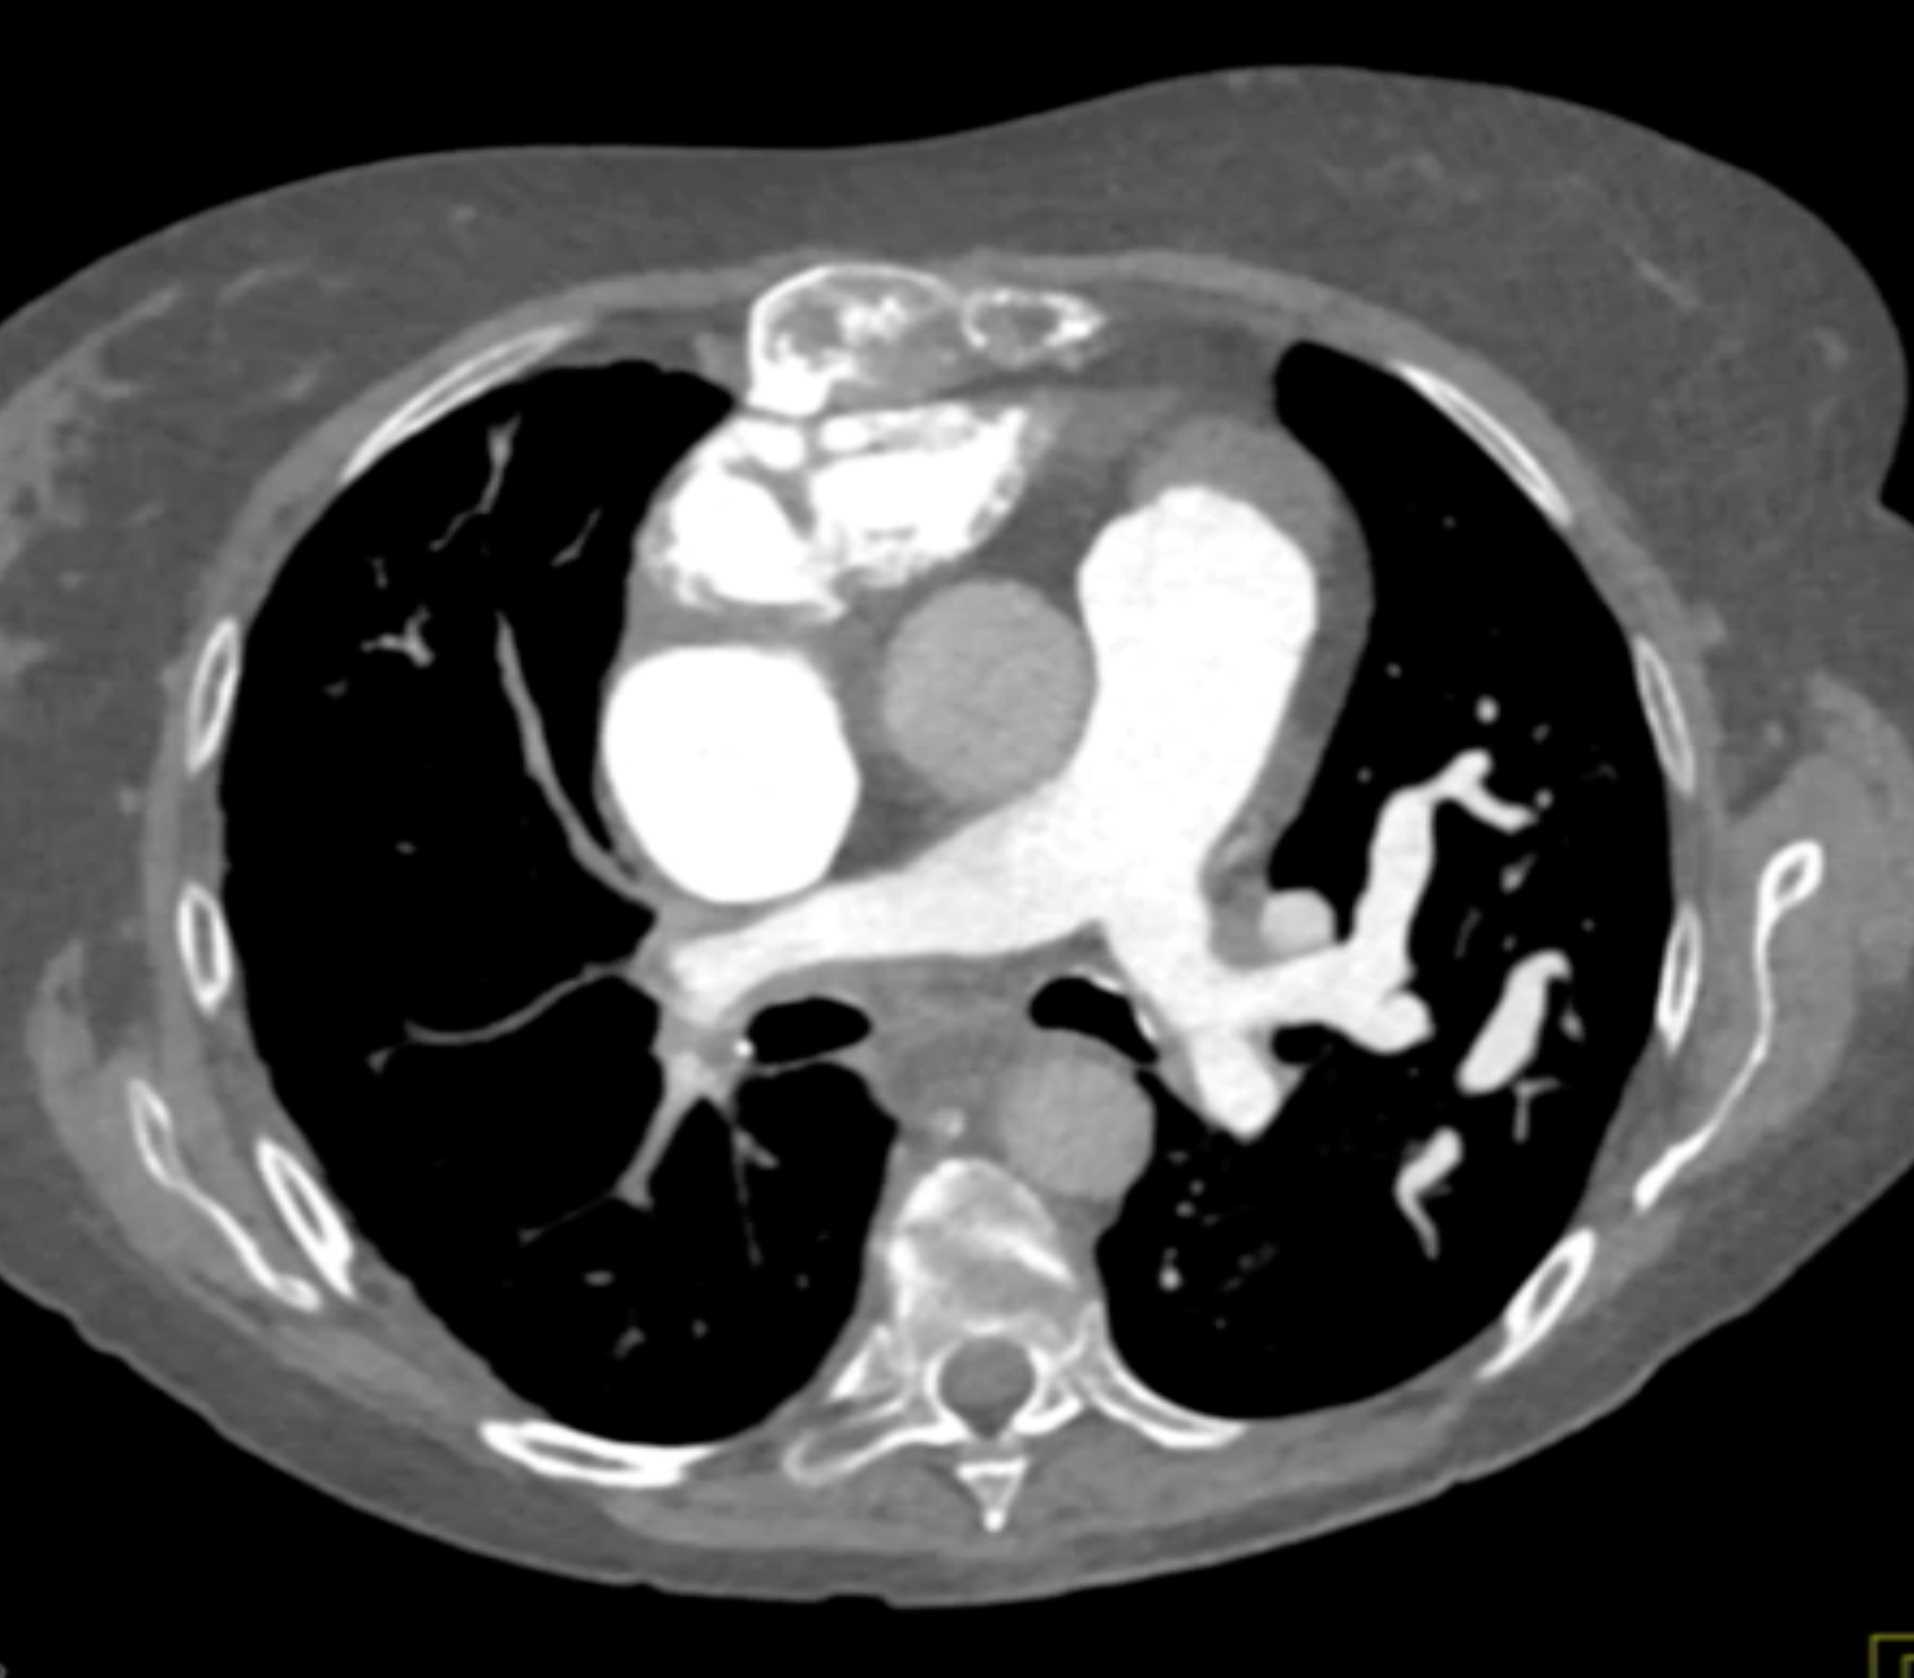

Thymic Carcinoma